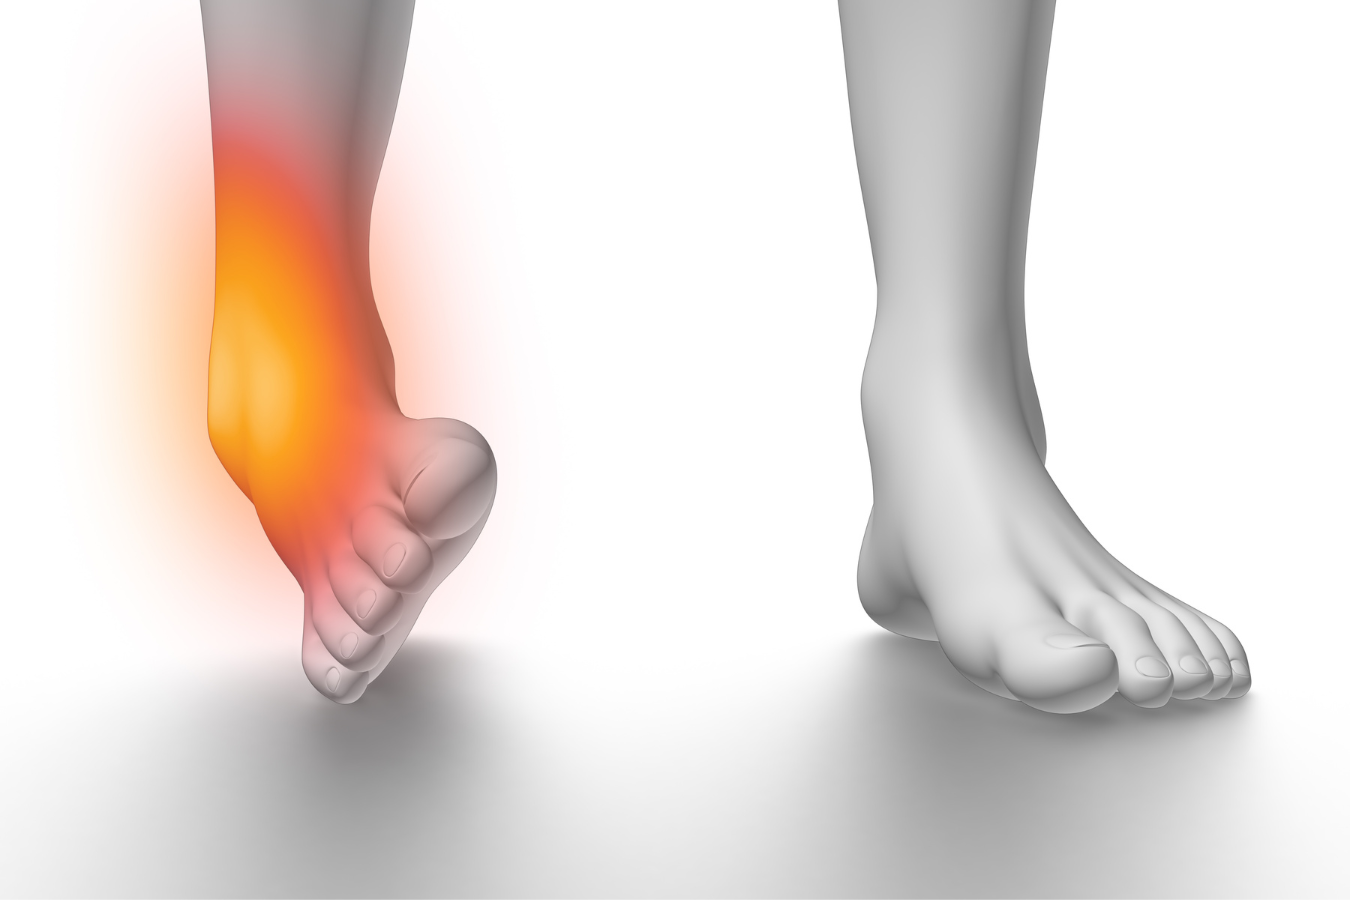

Achilles tendon injuries healthdirect 2025, Achilles Pain After Ankle Sprain Rehab 49 2025, Achilles Tendon Strain vs Sprain 2025, Strain vs Sprain What is the Difference 2025, Achilles Tendinitis Ankle Pain Foot Injury 2025, Achilles Pain After Ankle Sprain Rehab 49 2025, Achilles Tendon Pain Symptoms Causes Treatment Exercises 2025, Achilles Tendon Injuries Johns Hopkins Medicine 2025, Achilles Rupture Physiopedia 2025, Achilles Tendon Pain Causes Treatments Prevention 2025, Know the Symptoms of Achilles Tendonitis Tendinopathy Gait Happens 2025, Achilles tendon Overview Mayo Clinic Orthopedics Sports Medicine 2025, Achilles Pain While Running What It Means and What to Do 2025, Achilles tendon rupture Bupa UK Symptoms and treatment 2025, JCM Free Full Text Foundational Principles and Adaptation of 2025, Achilles Tendonitis Treatment Recovery Foot Pain Explored 2025, Anterior Talofibular Ligament Sprain 2025, Achilles Tendonitis Consultant Mr Andrew Roche FRCS London 2025, Micro tears of the Legs Strongest Tendon the Achilles 2025, Ankle Sprain NHS Lanarkshire 2025, Tendon Injuries of the Foot and Ankle Cal Sports Orthopaedic 2025, Sudden Ankle Pain Without an Injury Causes and Treatment 2025, Sprained Ankles Highgate Podiatry Biomechanics Orthotic Insoles 2025, Peroneal Tendinitis Symptoms Causes Diagnosis Treatments 2025, Sprained Ankle Treatment Rehabilitation Exercises 2025, Achilles Tendinopathy Causes Symptoms Treatment The Feet 2025, Sprained ankle Wikipedia 2025, Physiotherapy in Calgary for Achilles Tendon Problems 2025, Achilles tendon pain Achilles Tendonitis Move Osteopathy 2025, Ankle Sprain Foot Ankle Orthobullets 2025, Twisted Ankle sprain is it alright to walk with pain and 2025, Heel Pain Podiatrist in Old Bridge and Sayreville NJ Jason Grossman DPM 2025, Foot and Ankle Pain Keeping Me Well 2025, 4 Heel Pain Symptoms to Take Seriously Chicagoland Foot and Ankle 2025, Sudden Ankle Pain Without an Injury Causes and Treatment 2025, What Causes A Sore Achilles Tendon How Is It Treated by Usman 2025, Sprained Ankle vs. Rolled Ankle Advanced Ortho and Spine 2025, Achilles tendon pain Causes. when to see a doctor and treatment 2025, Best Ankle Braces for Sprains The Bracing Experts 2025, Tendinopathy Symptoms Causes Treatment 2025, Achilles Injuries Treatment Penn Medicine 2025, Ankle Sprains for Teens Nemours KidsHealth 2025, Achilles tendon pain Causes. when to see a doctor and treatment 2025, How to Heal a Ankle Injury using Sprain Ankle Treatment 2025, Hurt Your Ankle Use Our Ankle Pain Symptom Checker Tool 2025, How Do You Know if You Have Damaged Your Achilles Tendon 2025, Tips and Tricks Following a Sprained Ankle 2025, Common running ankle injuries everything you need to know 2025, Ankle Pain ankle ligaments sprain Everything You Need To Know Dr. Nabil Ebraheim 2025, Achilles Tendon Injury How Much Compensation Could I Claim 2025.

Twisted ankle achilles tendon pain 2025